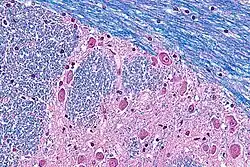

Micrograph of the pons using a hematoxylin & eosin-luxol fast blue stain.

Typically, cresyl violet is used as counterstain. Cresyl violet binds to Nissl substance, which is concentrated around a neural cell's nucleus; such a counterstain allows differentiation between myelenated axons, cell bodies, and unmyelenated axons or glial cells. In such a stain, myelin fibers appear blue, neuropil appears pink (or faint purple), and neuron cell bodies appear purple.

Though the typical counterstain for LFB staining is cresyl violet, LFB protocols are frequently combined with other common staining methods. The combination of LFB with counterstain or other staining methods provides the most useful and reliable method for the demonstration of pathological processes in the CNS.[23] After cresyl violet, LFB is most often combined with H&E stain (hematoxylin and eosin), which is abbreviated H-E-LFB, H&E-LFB. Other common staining methods include the periodic acid-Schiff, Oil Red O, phosphotungstic acid, and Holmes silver nitrate method.[23]